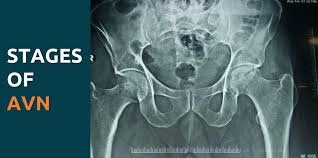

Avascular necrosis (AVN) occurs when blood supply to a bone is disrupted, leading to bone tissue death and joint pain. Therefore, timely medical intervention is essential to prevent further joint damage. Patients in Bhandara seeking AVN treatment often require a combination of diagnostic evaluation, non-surgical management, and sometimes surgical procedures. Moreover, early treatment can preserve joint function and delay or prevent the need for joint replacement. As a result, patients regain mobility and reduce discomfort in daily life.

AVN, also known as osteonecrosis, typically affects the hip but can involve other joints such as the knee or shoulder. The condition develops when blood flow to the bone is compromised, causing bone cells to die. Consequently, the bone weakens and collapses, leading to joint pain and stiffness. Moreover, risk factors such as long-term steroid use, excessive alcohol intake, trauma, and certain medical conditions increase susceptibility. Therefore, early diagnosis is crucial to prevent irreversible joint damage.

Accurate diagnosis is the foundation of effective AVN treatment. At Varunam hospital, Bhandara, patients undergo clinical examination, X-rays, MRI scans, and sometimes CT scans to assess bone and joint integrity. MRI is particularly useful for detecting early-stage AVN before bone collapse occurs. Dr. Utsav Agrawal provides professional oversight in interpreting results and formulating individualized treatment plans. Therefore, patients receive precise diagnosis and targeted care.